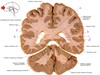

9

Q

a

Body of corpus callosum

10

b

septum pellucidum

11

c

Corona radiata

12

d

Anterior horn of lateral ventricle

13

e

Globus pallidus

14

f

Anterior commissure

15

g

Optic chiasm

16

h

Optic tract

17

i

Uncus

18

j

19

k

20

L

Putamen

21

m

Anterior limb of internal capsule

22

n

Head of caudate nucleus